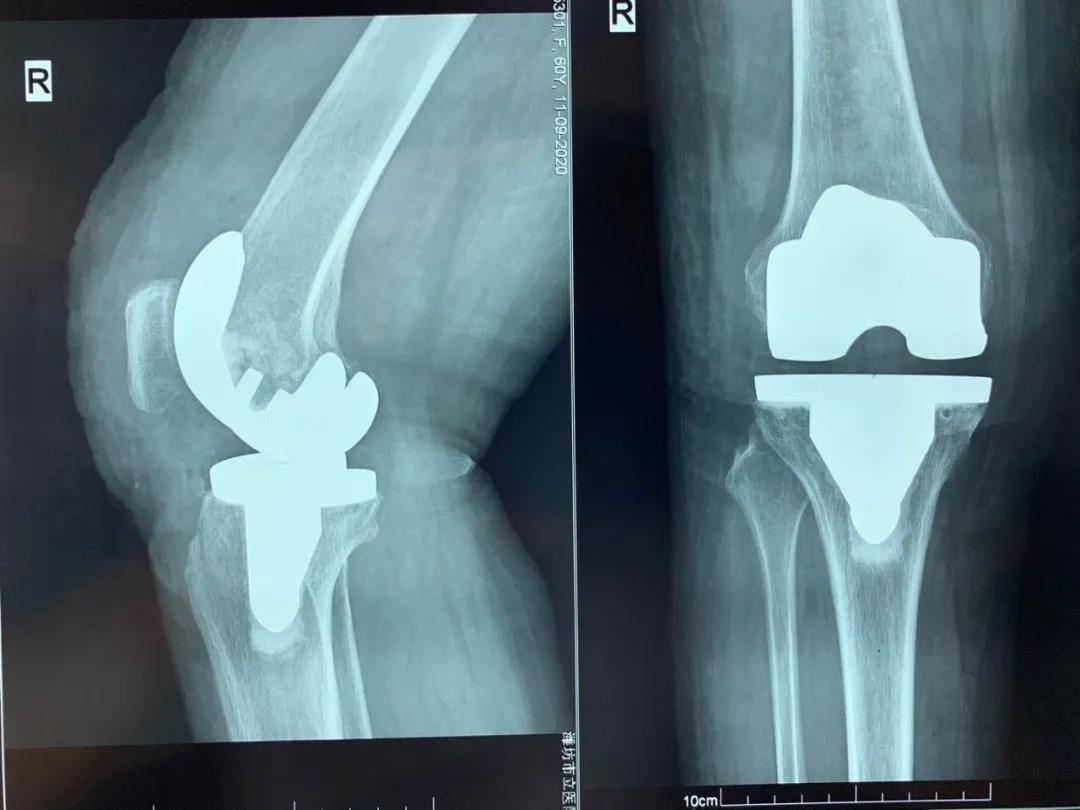

手術(shù)前

手術(shù)后